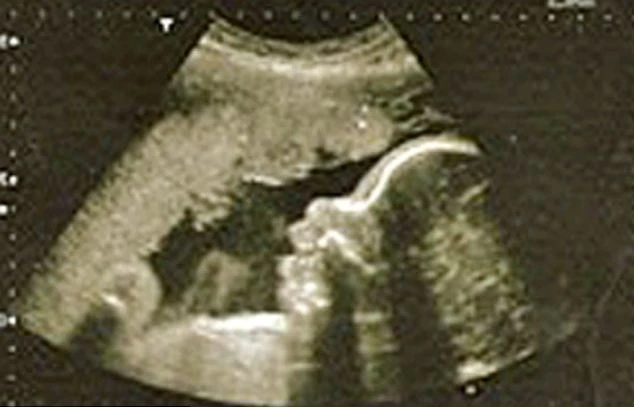

(Kiến Thức) - Thiên thần bé nhỏ đáng yêu này chưa chào đời mà đã cứu được mẹ khỏi khối u có khả năng gây ung thư.

Người phụ nữ may mắn này tên là Nicola Weller, 29 tuổi. Cô phải nhập viện để phẫu thuật cắt bỏ một khối u trong tử cung. Nhưng thật không ngờ, kết quả xét nghiệm cho thấy cô đã mang thai.

Đồng thời các bác sĩ tại bệnh viện Bệnh viện Dorset County cũng phát hiện ra hormone mang thai làm cho khối u tự phân hủy, nghĩa là cô Weller không cần tiếp nhận bất kỳ hình thức điều trị nào nữa.

Bé Brandon được sinh ra hoàn toàn khỏe mạnh vào tháng 9 năm 2010.

Đến nay, vẫn không hề có bất kỳ dấu hiệu nào cảnh báo sự trở lại của khối u.

Tuy cả mẹ và bé Brandon đều khỏe mạnh nhưng họ vẫn thường xuyên tiến hành kiểm tra sức khỏe định kỳ để sớm có phát hiện nếu có bất kỳ dấu hiện lạ nào.